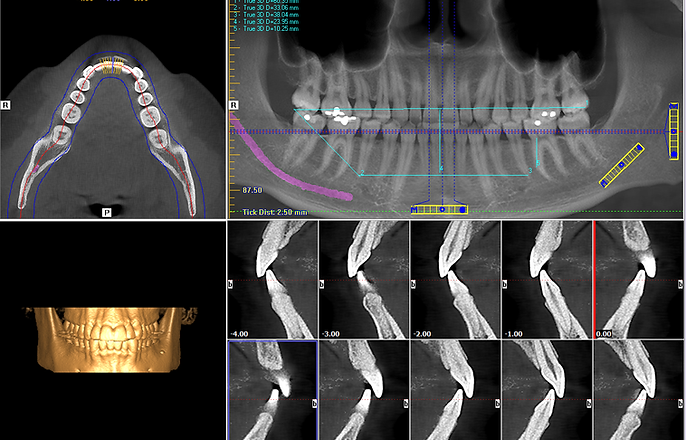

Welcome to West Side Imaging Centers, where cutting-edge technology meets compassionate care! At our state-of-the-art facility, we specialize in advanced imaging services tailored to address specific healthcare needs. Whether you’re seeking diagnosis and treatment options for Sleep Apnea or TMJ-related concerns, our dedicated team of professionals is here to support you on your journey to better health.

With a focus on precision and accuracy, we provide comprehensive imaging solutions that empower you and your healthcare provider to make informed decisions. Your well-being is our top priority, and we are committed to delivering exceptional service in a comfortable and welcoming environment. Trust us to be your partner in health, guiding you towards a brighter, healthier future. Welcome to a place where your health and comfort are our primary concern – welcome to West Side Imaging Centers.

Rest assured that we understand our patients’ concerns regarding radiation dose exposure and safety. The i-CAT FLX is the most advanced CBCT x-ray machine on the market. Please see our chart on this page for a comparison of our i-CAT image radiation exposure vs. other radiation sources of exposure. There has not been any documentation of someone injured by dental CBCT technology (cone beam computed tomography).